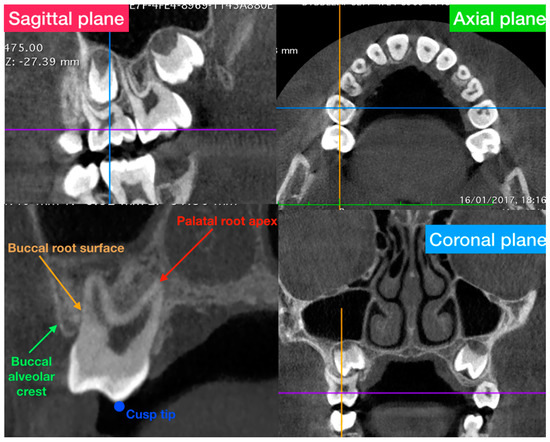

- Buccal alveolar bone thickness (BT), defined as the distance between the buccal root surface and the outer border of the alveolar bone, along a horizontal line passing through the furcation;

- Buccal alveolar bone height (BH), defined as the distance between the buccal or mesio-buccal cusp tip and the buccal alveolar bone crest;